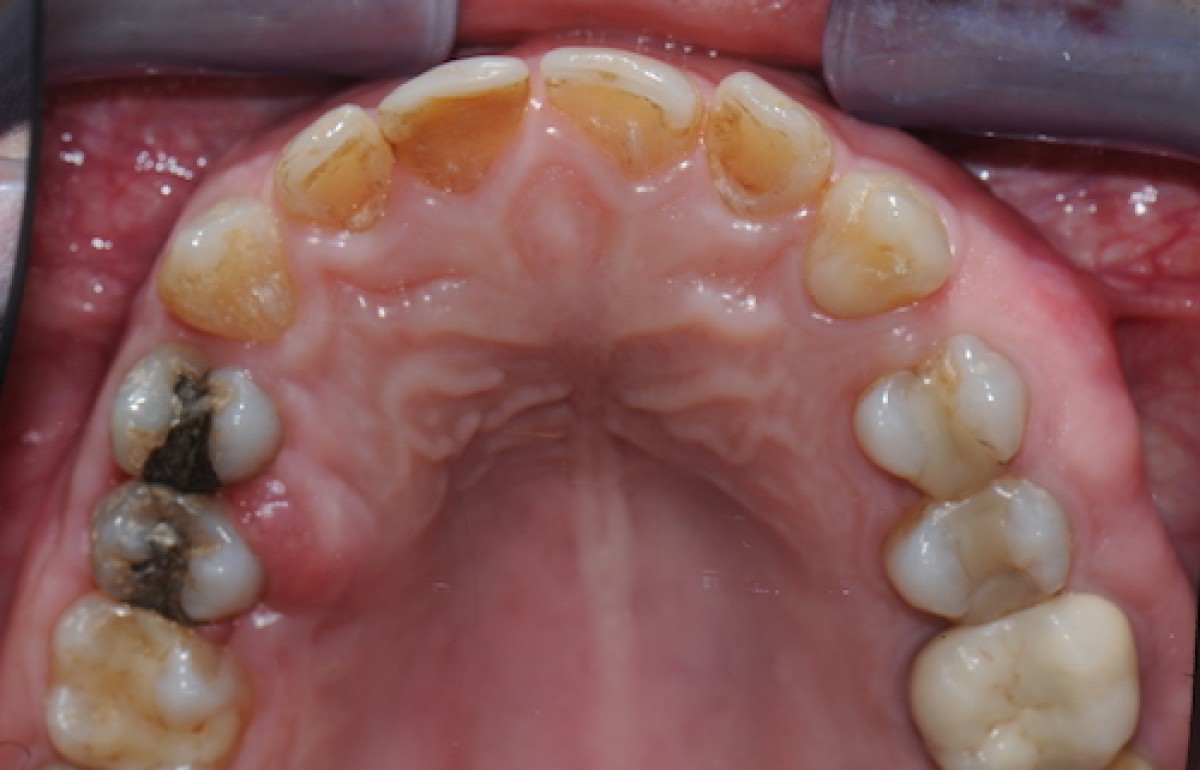

GDD is a rare autosomal dominant syndrome caused by mutations of the ANO 5 gene, which is located on chromosome 11. The most frequent clinical signs are: maxillary fibro-osseous lesions, bone fragility, diaphyseal cortical thickening and bowing of long bones. The syndrome was described for the first time in literature by Akasaka in 1969, however the etiopathogenesis and the clinical features remain largely undescribed. There is great variability between patients and the genetic screening is at present the only reliable diagnostic tool. The patients described in this paper were diagnosed with GDD on the basis of bone alterations and genomic analysis showing a heterozygous missense mutation of the ANO 5 gene (ANO 5 can also be called TMEM16E). We decided to use a conservative treatment: patient 1 underwent the surgical removal of jaw exostosis as a result of the disabling effect of the malformation and the mandibular right third molar of patient 2 was extracted because it was symptomatic. Neither of the patients experienced complications during either the surgery or the postoperative period.